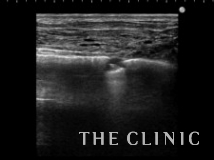

エコー下にヒアルロニダーゼで溶解、吸引しました。

ほとんどなくなりました。